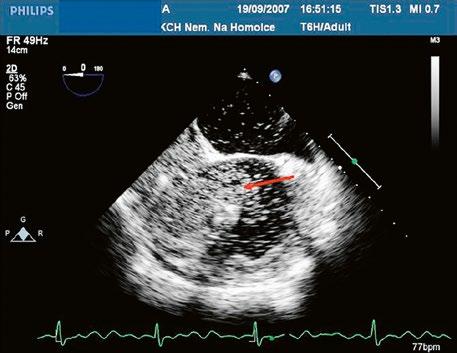

z Defekt síňového septa typu sinus venosus superior: 9 %, v místě vústění horní duté žíly (HDŽ), která na defekt nasedá, téměř vždy je spojen s parciálním anomálním návratem pravostranných plicních žil do HDŽ nebo do pravé síně (kap. 45.18 Anomální návrat plicních žil (Obr. 45.3, Obr. 45.4, Video 45.3, Video 45.4).

Obr. 45.3 Defekt septa síní typu sinus venosus superior, TEE nad úrovní aortální chlopně, defekt je v horní části septa označen křížky

AO – aorta, LS – levá síň, PS – pravá síň

Obr. 45.4 Defekt typu sinus venosus superior s levopravým zkratem v barevném dopplerovském mapování. TEE v longitudinální projekci, defekt se nachází v horní části septa, je označen žlutou šipkou, na něj nasedá horní dutá žíla (HDŽ)

AP – plicnice, LS – levá síň, PS – pravá síň